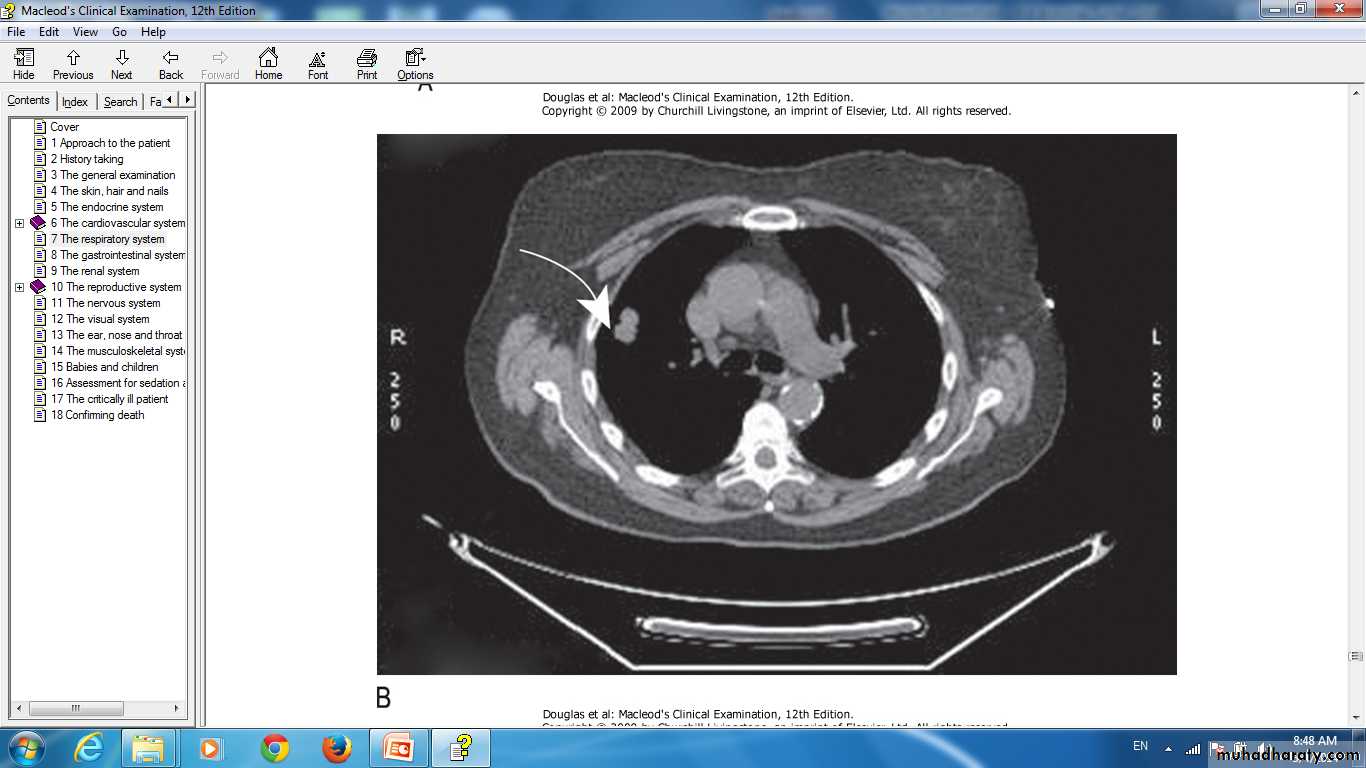

Lung cancer in right lung CT scan of thorax.